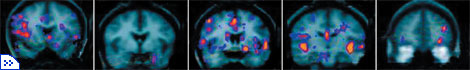

Томографические изображения мозга кокаинистов. |